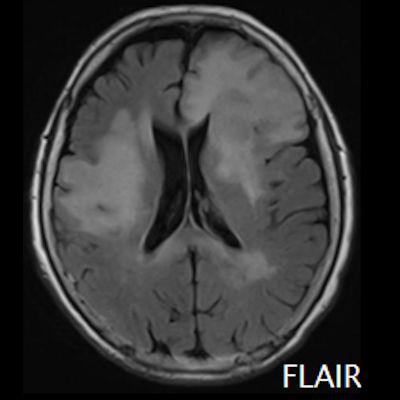

- (A) Her iki periventriküler beyaz cevherde aksiyel T2A, FLAIR serilerde hiperintens, T1A hipointens geniş ödem alanları (oklar) izlenmektedir. Sol frontalde T2A’da hipointens kitle lezyonuna (ok) dikkat ediniz.

- Genellikle supratentoriyal alanda, bazal ganglion, periventriküler beyaz cevher, orta hat ve korpus kallozum vb. yerleşme eğiliminde tek veya multipl kitleler şeklinde görülür.

- MRG’de, lenfomalar tipik olarak T2A sekanslarda hipointens olup DAG’de belirgin difüzyon kısıtlanması gösterirler.